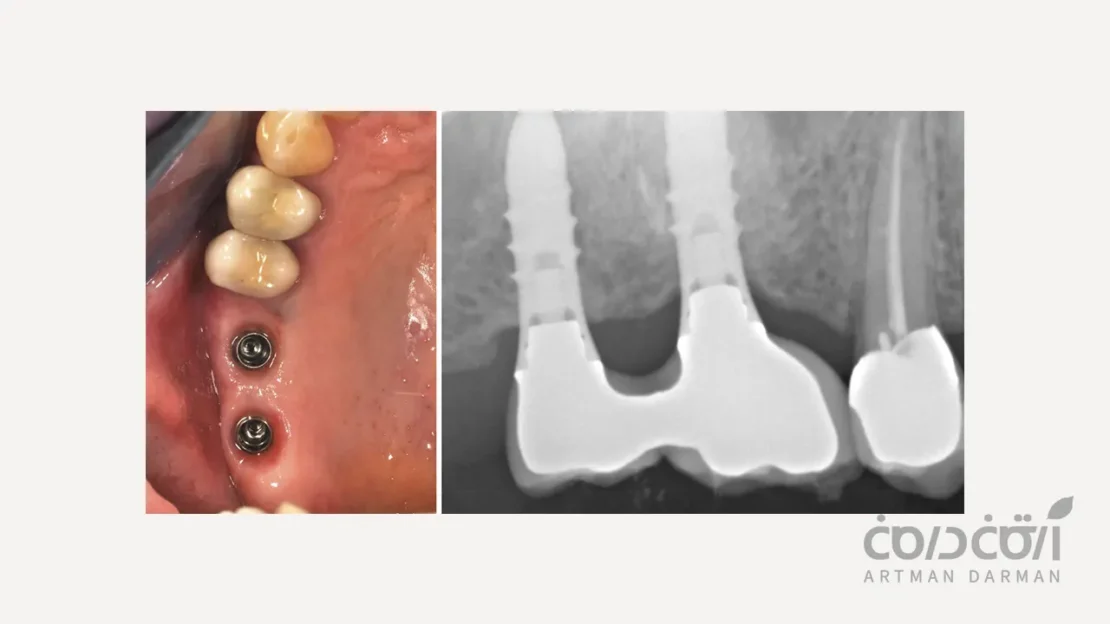

شرکت در جلسات چکاپ و نگهداری منظم

این جلسات (معمولاً هر ۶ ماه یکبار) به اندازه جراحی اولیه اهمیت دارند. در این ویزیت ها:

- دندانپزشک وضعیت لثه و استخوان اطراف ایمپلنت را با پروبینگ و رادیوگرافی بررسی می کند.

- پروتز را چک می کند.

- و یک جرم گیری اصولی برای حذف پلاک ها و جرم های سخت شده انجام می دهد.

- این جلسات به طور کلی به تشخیص زودهنگام هرگونه مشکلی قبل از پیشرفت آن کمک می کند.